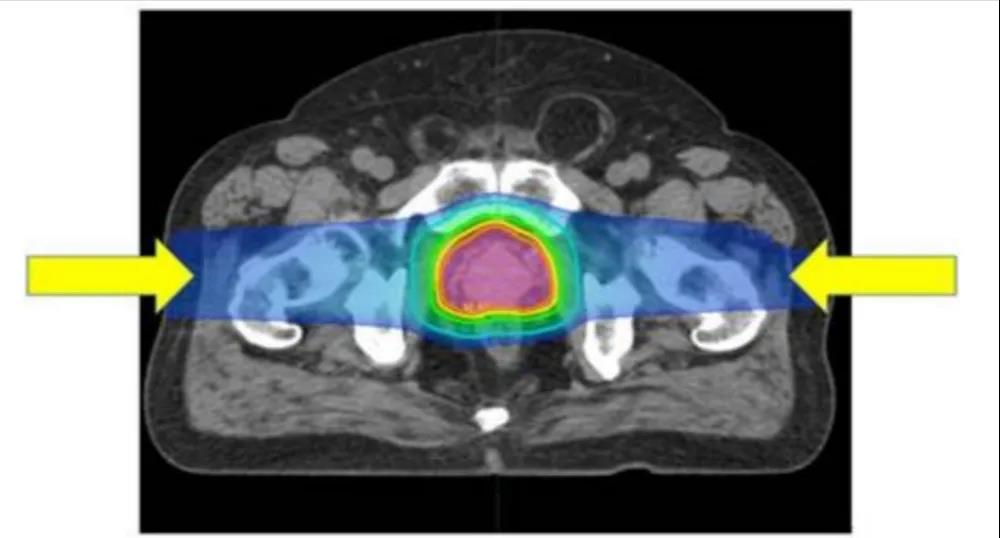

通過從左右兩個方向照射,質(zhì)子治療可獲得集中在前列腺癌的良好劑量分布

三維適形光子放療(3D-CRT)和質(zhì)子治療的劑量分布